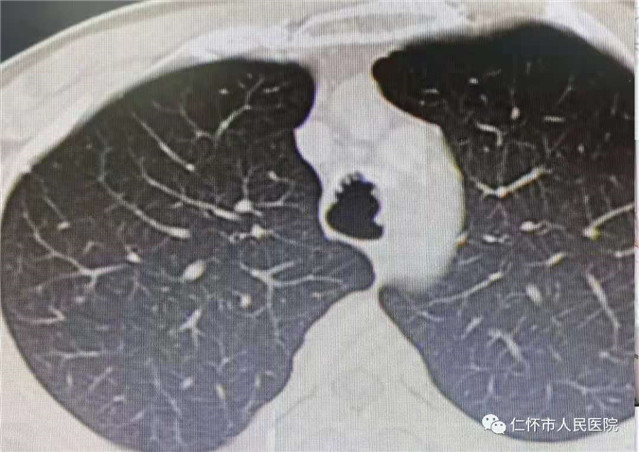

近日,我院呼吸与危重症医学科收治了一位中年男性患者,母××,44岁,该患者因“反复咳嗽、咳痰2月”入院。行胸部CT发现右肺中叶、双肺下叶多发小斑片状密度增高影,气管壁多发结节状影,考虑双肺感染,气管壁多发结节。入院后予积极抗感染及止咳对症治疗,针对患者气管壁多发结节,拟完善支气管镜检查明确病因。

影像学表现

胸部X线以及普通的厚层CT对本病不敏感。薄层CT对气管、支气管壁结节内的钙化影相当敏感。气管、主支气管内多发的黏膜下小结节钙化影并突向管腔是TO较具特征性的CT表现。结节直径通常为1—10mm,位于气管和主支气管的前壁和侧壁,无蒂或有蒂,可散发或融合成片,质硬,触之易出血,黏膜可正常、充血、灰白、小血管显露或呈粉红色钟乳石样,管腔可变窄或不规则,后壁(气管膜部)极少受累,声门及声门以上组织、叶支气管及其远端支气管也很少受累。